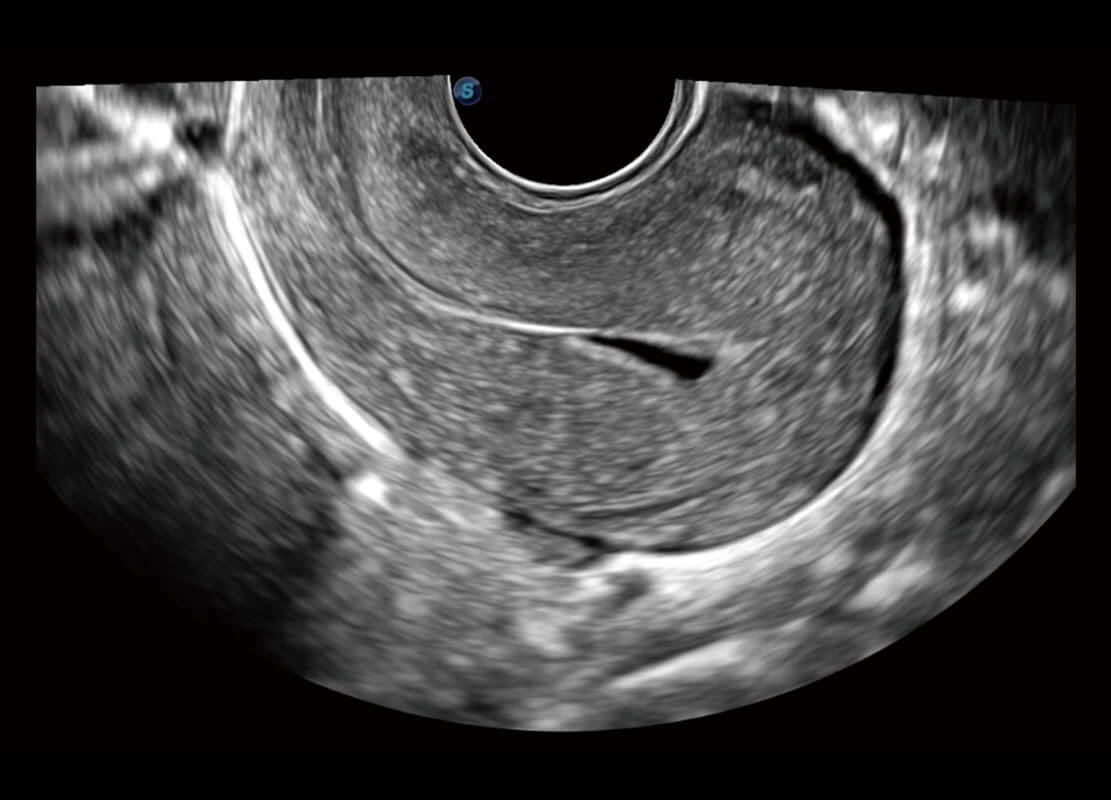

腔内妇科-卵巢